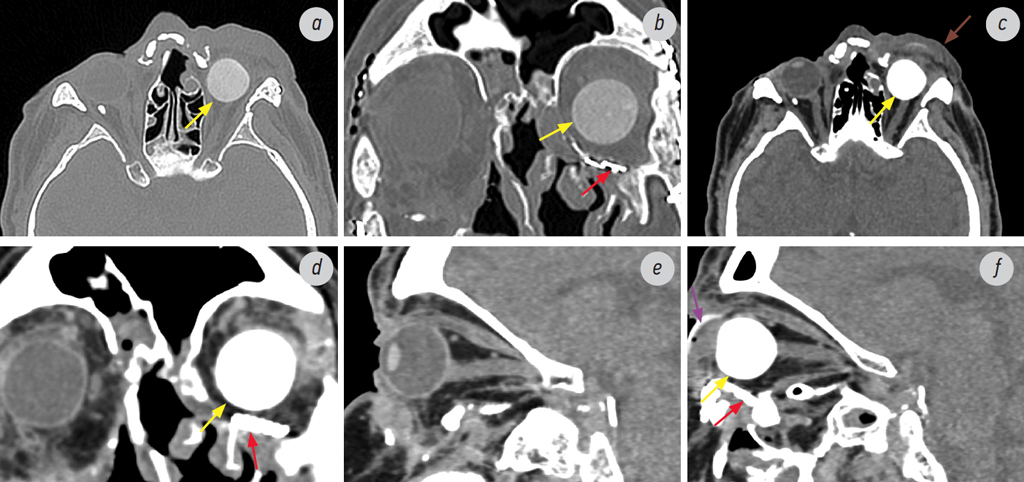

Рис. 3. Состояние после эндопротезирования левой орбиты. Мультиспиральная компьютерная томография: а — аксиальный срез, режим костного окна; b — корональный срез, режим костного окна; c — аксиальный срез, режим мягкотканного окна; d — корональный срез, режим мягкотканного окна; e, f — сагиттальный срез, режим мягкотканного окна. Состояние после эндопротезирования левого глазного яблока и установки пластины в области нижней стенки левой орбиты (красная стрелка): в полости левой орбиты определяется эндопротез (жёлтая стрелка) сферической формы с подшитыми к капсуле эндопротеза прямыми глазодвигательными мышцами — сформированная опорно-двигательная культя, кнаружи от которой определяется наружный косметический протез (фиолетовая стрелка). После эндопротезирования сохраняются выраженные посттравматические деформации мягких тканей лица, в области периорбитальных тканей слева также отмечается увеличение объёма и уплотнение тканей (коричневая стрелка)

Fig. 3. Condition after endoprosthetics of the left orbit. MSCT: a — axial slice, bone window mode; b — coronal slice, bone window mode; c — axial slice, soft tissue window mode; d — coronal slice, soft tissue window mode; e, f — sagittal slice, soft tissue window mode. Condition after endoprosthetics of the left eyeball and mesh installation in the area of the left lower orbital wall (red arrow): in the cavity of the left orbit an endoprosthesis (yellow arrow) of a spherical shape with direct oculomotor muscles sutured to the endoprosthesis capsule is determined — a formed musculoskeletal stump (MSS), outwards from the MSS an external cosmetic prosthesis is determined (purple arrow). After endoprosthetics, pronounced post-traumatic deformations of the soft tissues of the face remain; in the area of the periorbital tissues on the left, an increase volume and thickening of the tissues is also noted (brown arrow)